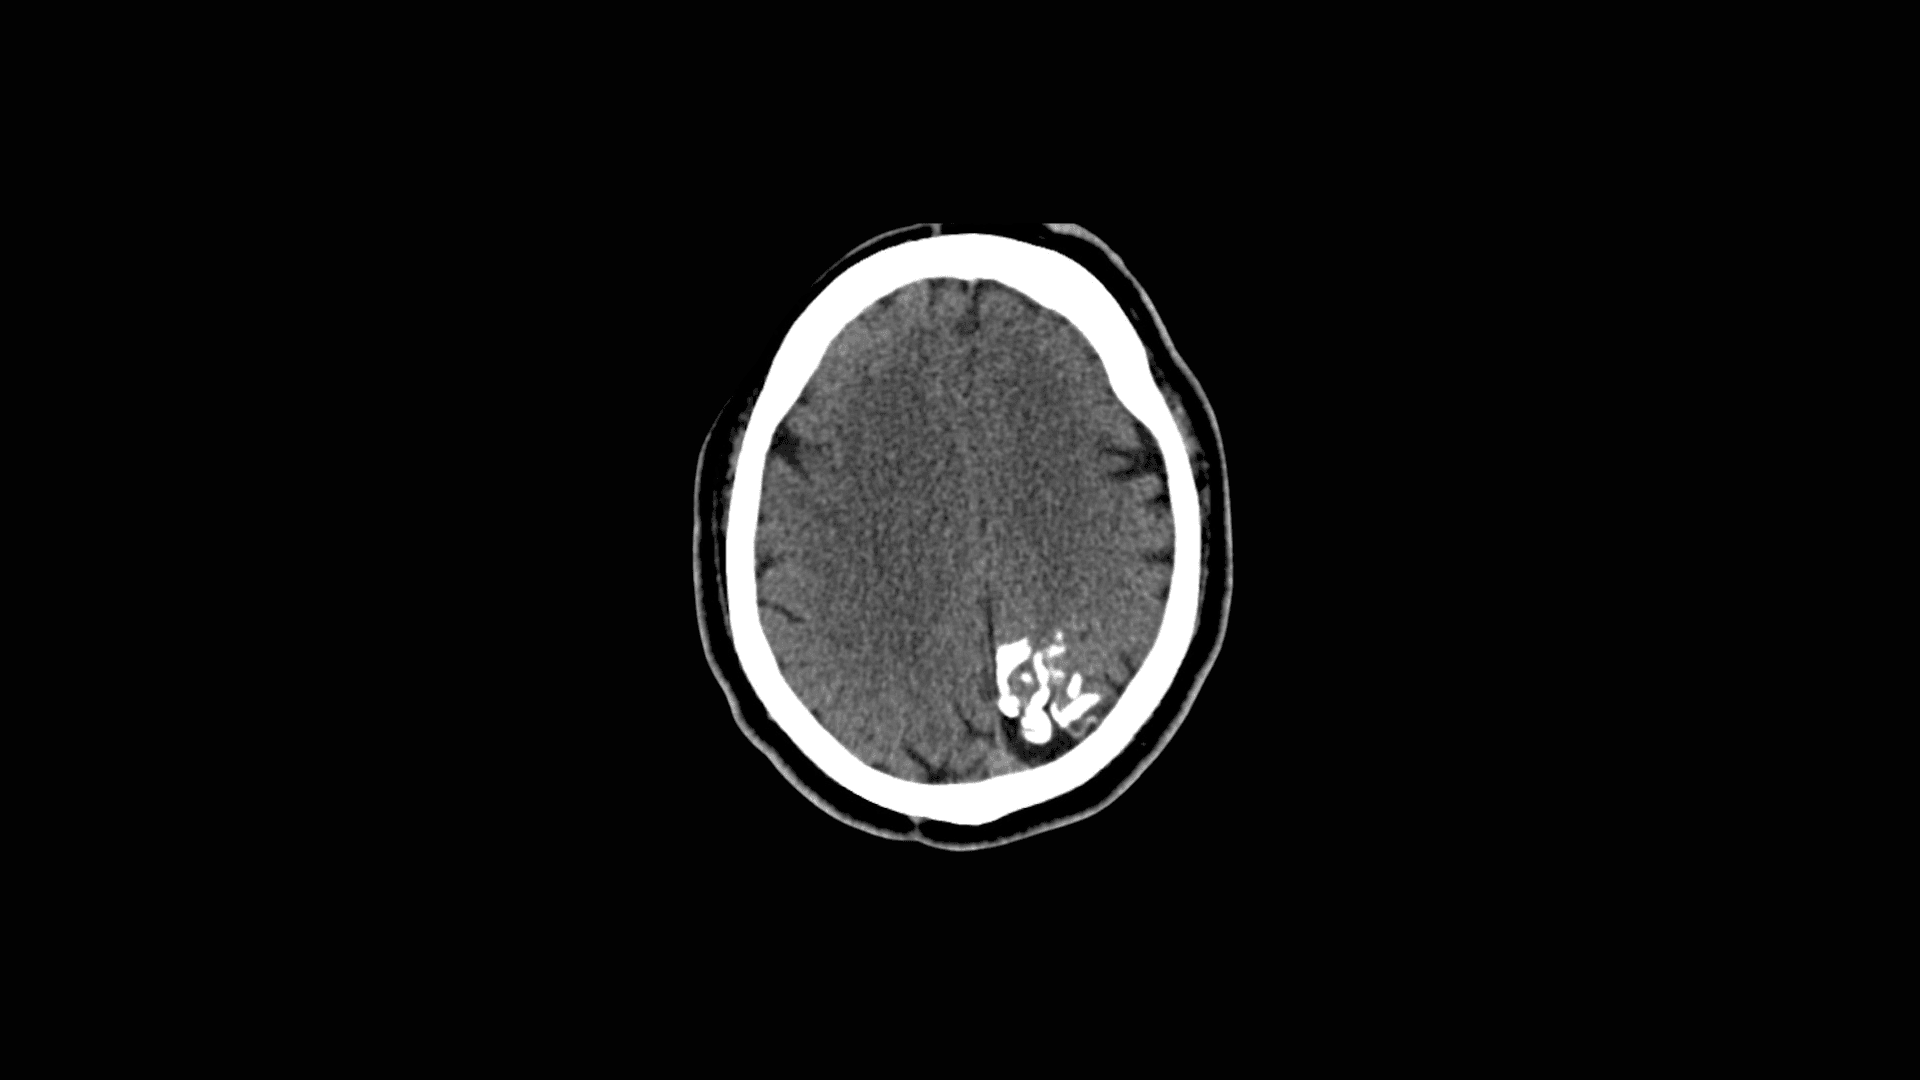

• CT-scan — het beste voor het detecteren van de kenmerkende gyriforme (spoorweg rails) verkalkingen